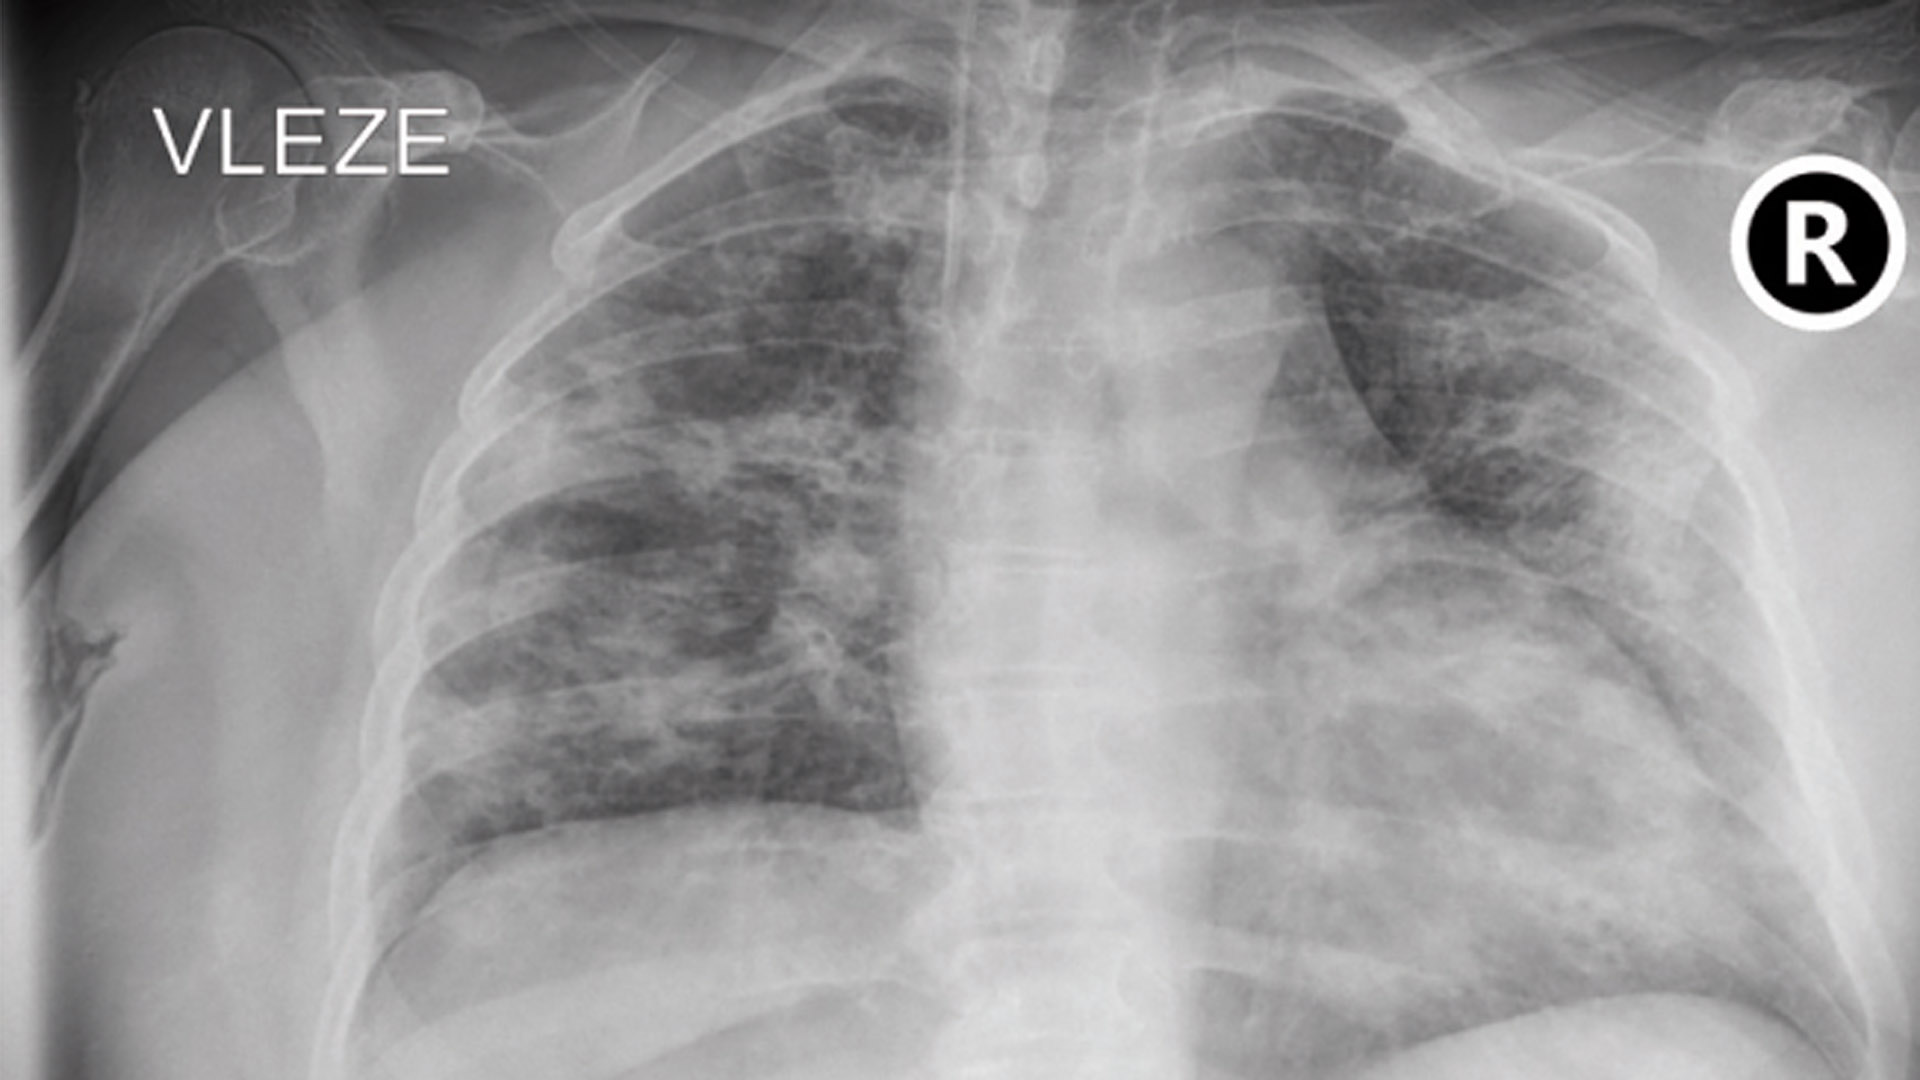

V průběhu léčby akutních covidových pacientů MLS laserem lékaři zaznamenali, jak v zahraničních studiích, tak ve vlastní praxi, výrazné proregenerační účinky. Diagnostika pomocí rentgenových snímků hovoří jasně – i stav již poškozené plicní tkáně se po aplikaci terapie většinou zlepšuje. Lasery se tak s odezníváním vlny epidemie přesunují k pacientům s novým onemocněním, s postcovidovým syndromem.

Michal Kopecký, vedoucí Centra postcovidové péče Fakultní nemocnice Hradec Králové, shrnuje, že se bohužel jedná o 10 procent osob, které covid-19 prodělaly, a to bez ohledu na to, zda se jednalo o mírný nebo těžký průběh. Nejčastěji si stěžují na dušnost, extrémní únavu, poruchy spánku a bolesti hlavy či kloubů. Stejnou zkušenost má i Lukáš Cibulka, který nyní místo akutních pacientů léčí ty postcovidové. Zatím eviduje přes 80 ukončených terapií, přičemž pouze čtyři osoby na léčbu nezareagovaly. Současně upozorňuje na rentgenologicky zjištěná masivní poškození plic i u pacientů, kteří prodělali covid-19 ve zdánlivě lehké formě v domácím ošetřování.